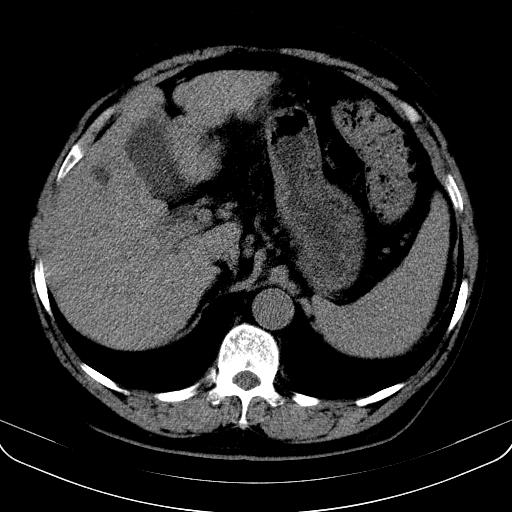

以下是引用jia119在2008-3-5 13:31:00的发言:[br]肝内多发片状低密度影,密度不均,我还是考虑肝ca可能,另肝内小囊肿,胆囊增大。

以下是引用形影不离在2008-3-5 12:18:00的发言:[br]肝硬化伴门脉高压征,肝内占位待排,增强再说.

以下是引用随光逐影在2008-3-5 21:11:00的发言:[br]肝硬化伴门脉高压(食管下段静脉曲张),肝癌不排除。建议:行ct增强扫描检查。

以下是引用同在2008-3-5 13:56:00的发言:[br]考虑肝癌可能性大,胆囊增大.